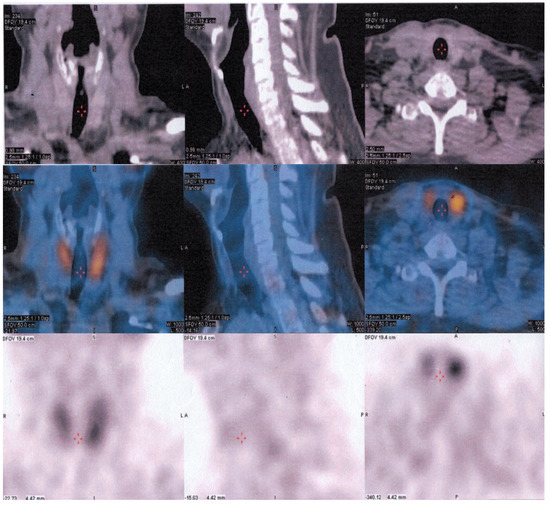

2.3. Imaging Findings

2.7. Follow-Up

- After parathyroidectomy, follow-up of patients with parathyroid cancer with 99mTc-sestaMIBI and 18-FDG PET/CT is necessary, especially in more aggressive and rapidly evolving forms.